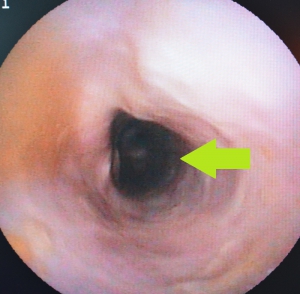

さらに食道は異物による内側からの圧迫に弱く、またその修復能力も高くありません。下の写真は異物を摘出した後のものですが、黄色矢印の先が凹んで周囲の粘膜から出血しています、その中央部は異物に圧迫されて潰瘍を作っています。また、緑矢印の先の赤黒い部分は粘膜面にうっ血が生じて、食道粘膜に広くダメージを起こしているのが分かります。

食道の損傷は食道炎を引き起こし、その結果、食道狭窄(きょうさく)や拡張、逆流性食道炎、嚥下困難などで、診断、治療の遅れは機能的ものも含めて深刻な後遺症を残す可能性が高まります。

下の2枚の写真は胸部食道のほぼ同じ場所を撮影した内視鏡画像です。左写真が正常な食道、右写真が重度の慢性食道炎の結果生じた食道狭窄の内視鏡写真です。左の正常と比べると食道の粘膜に激しい変化を生じているのが確認できます。